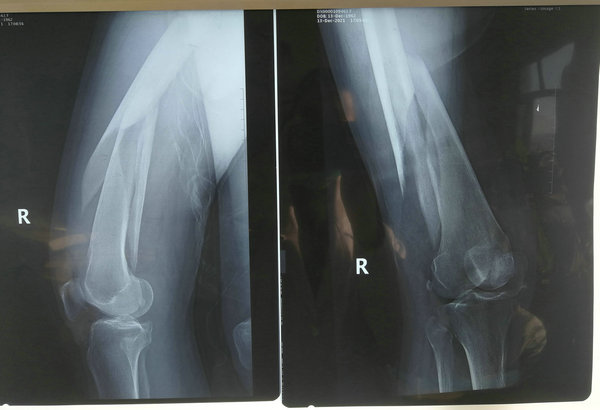

12月13日,58岁的乔阿姨和往常一样骑着电动车出门,就在行驶平稳的时候,一个不小心,电动车滑倒了,重重的电动车压在了乔阿姨的右腿上。随后乔阿姨被送往其他医院救治,经过一系列的检查,乔阿姨确诊为“股骨骨折”,这让性格开朗的乔阿姨不知所措,大腿断了,犹如晴天霹雳一般,想要重新站起来,只有通过手术治疗。

在受伤11天后,乔淑文被转到了齐医附属二院骨外科三病区治疗,接到病人后朱剑峰主任看了X线片之后,立刻组织科室人员开展会诊,拟定手术方案以及术前的准备。得知乔阿姨有心脏病史5年,并且有甲亢的既往史,入院时甲功各项指标均不在正常范围之内,这无疑为手术又增加了一定的难度,朱主任决定,等乔阿姨心功能及甲功降至能承受手术的时候,采取对患者伤害最小的手术方案——髓内针内固定,但乔阿姨骨折端靠近膝关节,常规的髓内针无法确切的固定,只能采用更新的技术——倒打髓内针。

术前影像